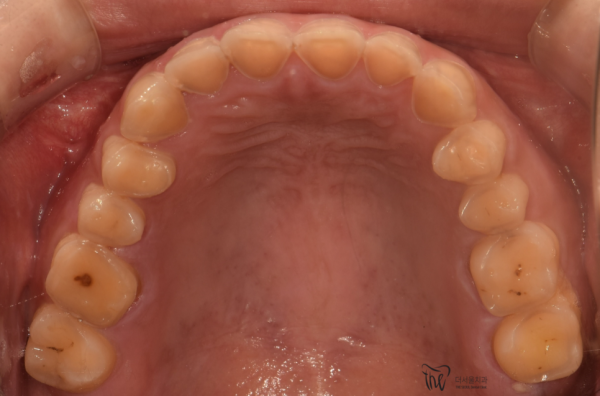

위의 환자분은 이렇게 교합면에서보면, 이미 법랑질이 모두 갈리고

상아질까지 드러나 있습니다. 상아질이 드러나게되면 이미 이가 많이 시렸을 텐데

이 환자분께서는 괜찮아지겠지 싶은 생각으로 참으셨다고 합니다.

이렇게 이가 시리거나, 턱이 얼얼한 느낌이 들면 치과에 빠르게 내원하셔야합니다.

If you look at the occlusal surface, the enamel is already split

There's even dentin. If the dentin was exposed, your teeth would have been cold

This patient endured with the thought of getting better.

If your teeth ache like this or your chin stings, you should visit the dentist quickly.